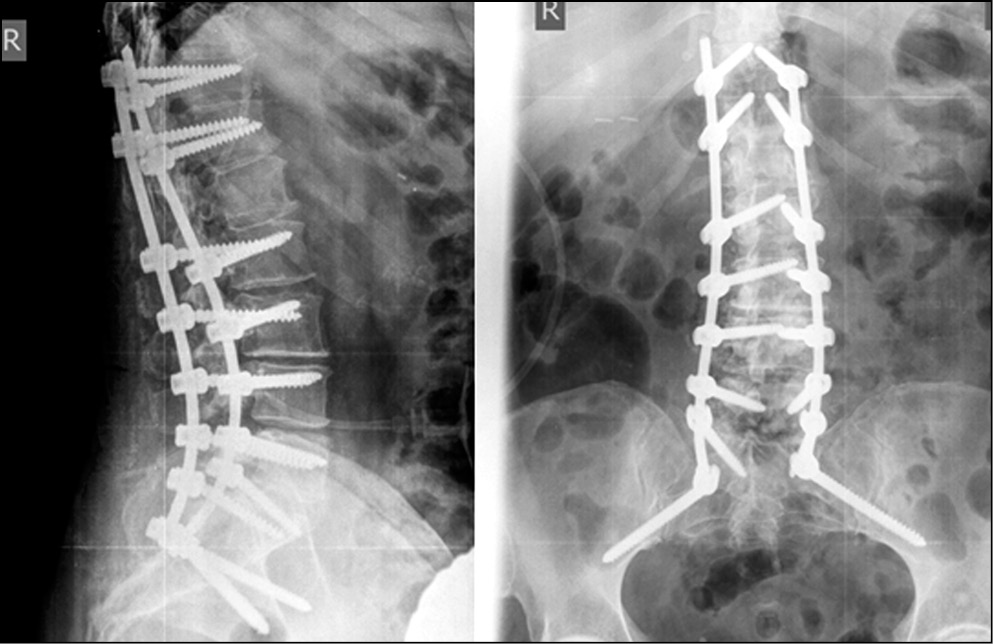

В 2020 г. А.А. Денисов и соавт. [62] подтвердили, что применение лордозирующих кейджей с углами 20–30° значительно увеличивает сегментарный лордоз и LL. Степень полученной коррекции сегментарного лордоза и LL была идентична прогнозируемым результатам (рис. 4, 5).

Рис. 4. Спондилограмма пациента с ADS до операции (из [62]). / Fig. 4. Spondylography of an ADS patient's spine before the surgery.

Рис. 5. Спондилограмма пациента с ADS. Выполнены протяженная транспедикулярная фиксация и передний спондилодез индивидуальными имплантами (из [62]). / Fig. 5. Spondylography of the same ADS patient. Extended transpedicular fixation and anterior spinal fusion are performed with the use of individual implants.

В случае если при нарушенном сагиттальном балансе отмечалась ретроверсия таза (большой PT), то после формирования правильного LL таз должен вернуться в правильное положение. Отсутствие такого изменения при послеоперационной величине PT >25° рассматривается как фактор высокого риска сохранения боли в поясничном отделе позвоночника и развития синдрома смежного сегмента.